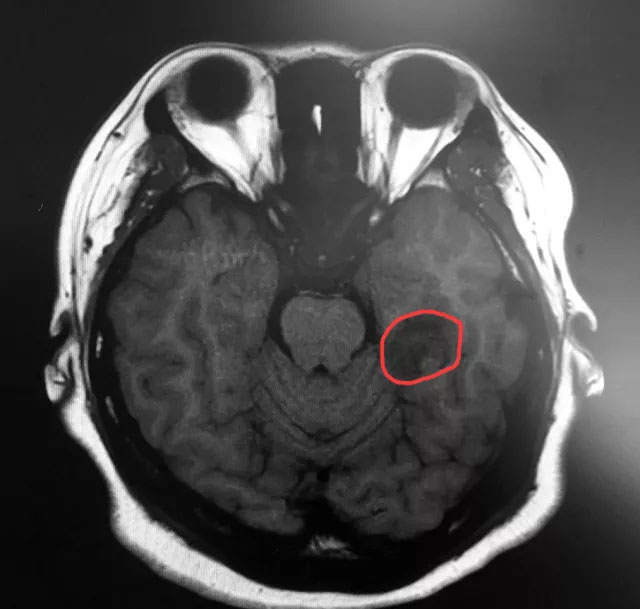

▲标记处为患者肿瘤部位

近日,上海蓝十字脑科医院神经外科6B病区收治了一名癫痫患者。今年三月初,25岁的袁女士(化名)突然出现“阵发性无法对答、闭目、呆立不动、吞咽唾液、意识丧失”等症状,一个月偶尔发作一次,当时患者和家人也没在意。但近三个月患者发作频繁,严重时一天多达三四次,家人明显感觉不对劲,之后就诊于当地医院,并进行了头部MRI检查,影像学显示:患者左侧颞叶(海马区)囊实性占位。